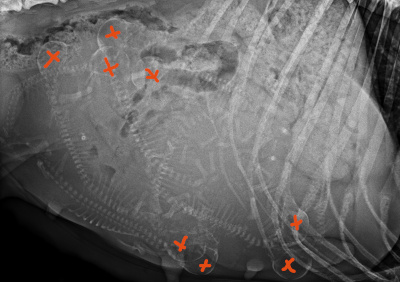

10.03.2025 – Tag 5️⃣8️⃣ Wie angekündigt waren wir heute zum röntgen. 8 Welpen sind es relativ sicher, eher könnte sich noch eins mehr verstecken.

Meine Ärztin ist aber recht sicher mit der Anzahl 8

D’Jamila wiegt jetzt 37,15kg, und hat damit auch bald die 8 kg, die man bei 8 Welpen im Durchschnitt rechnet zugelegt.